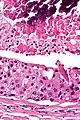

Low magnification micrograph of a salivary duct carcinoma with characteristic comedonecrosis (left of image) adjacent to normal parotid gland (right of image). H&E stain.

Salivary duct carcinoma (SDC) is a rare type of aggressive cancer that arises from the salivary glands.[1] It is predominantly seen in men and, generally, has a poor prognosis.[2] Other high grade carcinomas can mimic SDC. About 40-60% of SDC arise in pleomorphic adenomas.[3] Most, if not all, SDCs express androgen receptor by immunohistochemistry.[4] Therapeutically relevant genetic alterations include ERBB2/Her2 amplification, PIK3CA and/or HRAS mutations.[5][6]

Their histologic appearance is similar to ductal breast carcinoma.